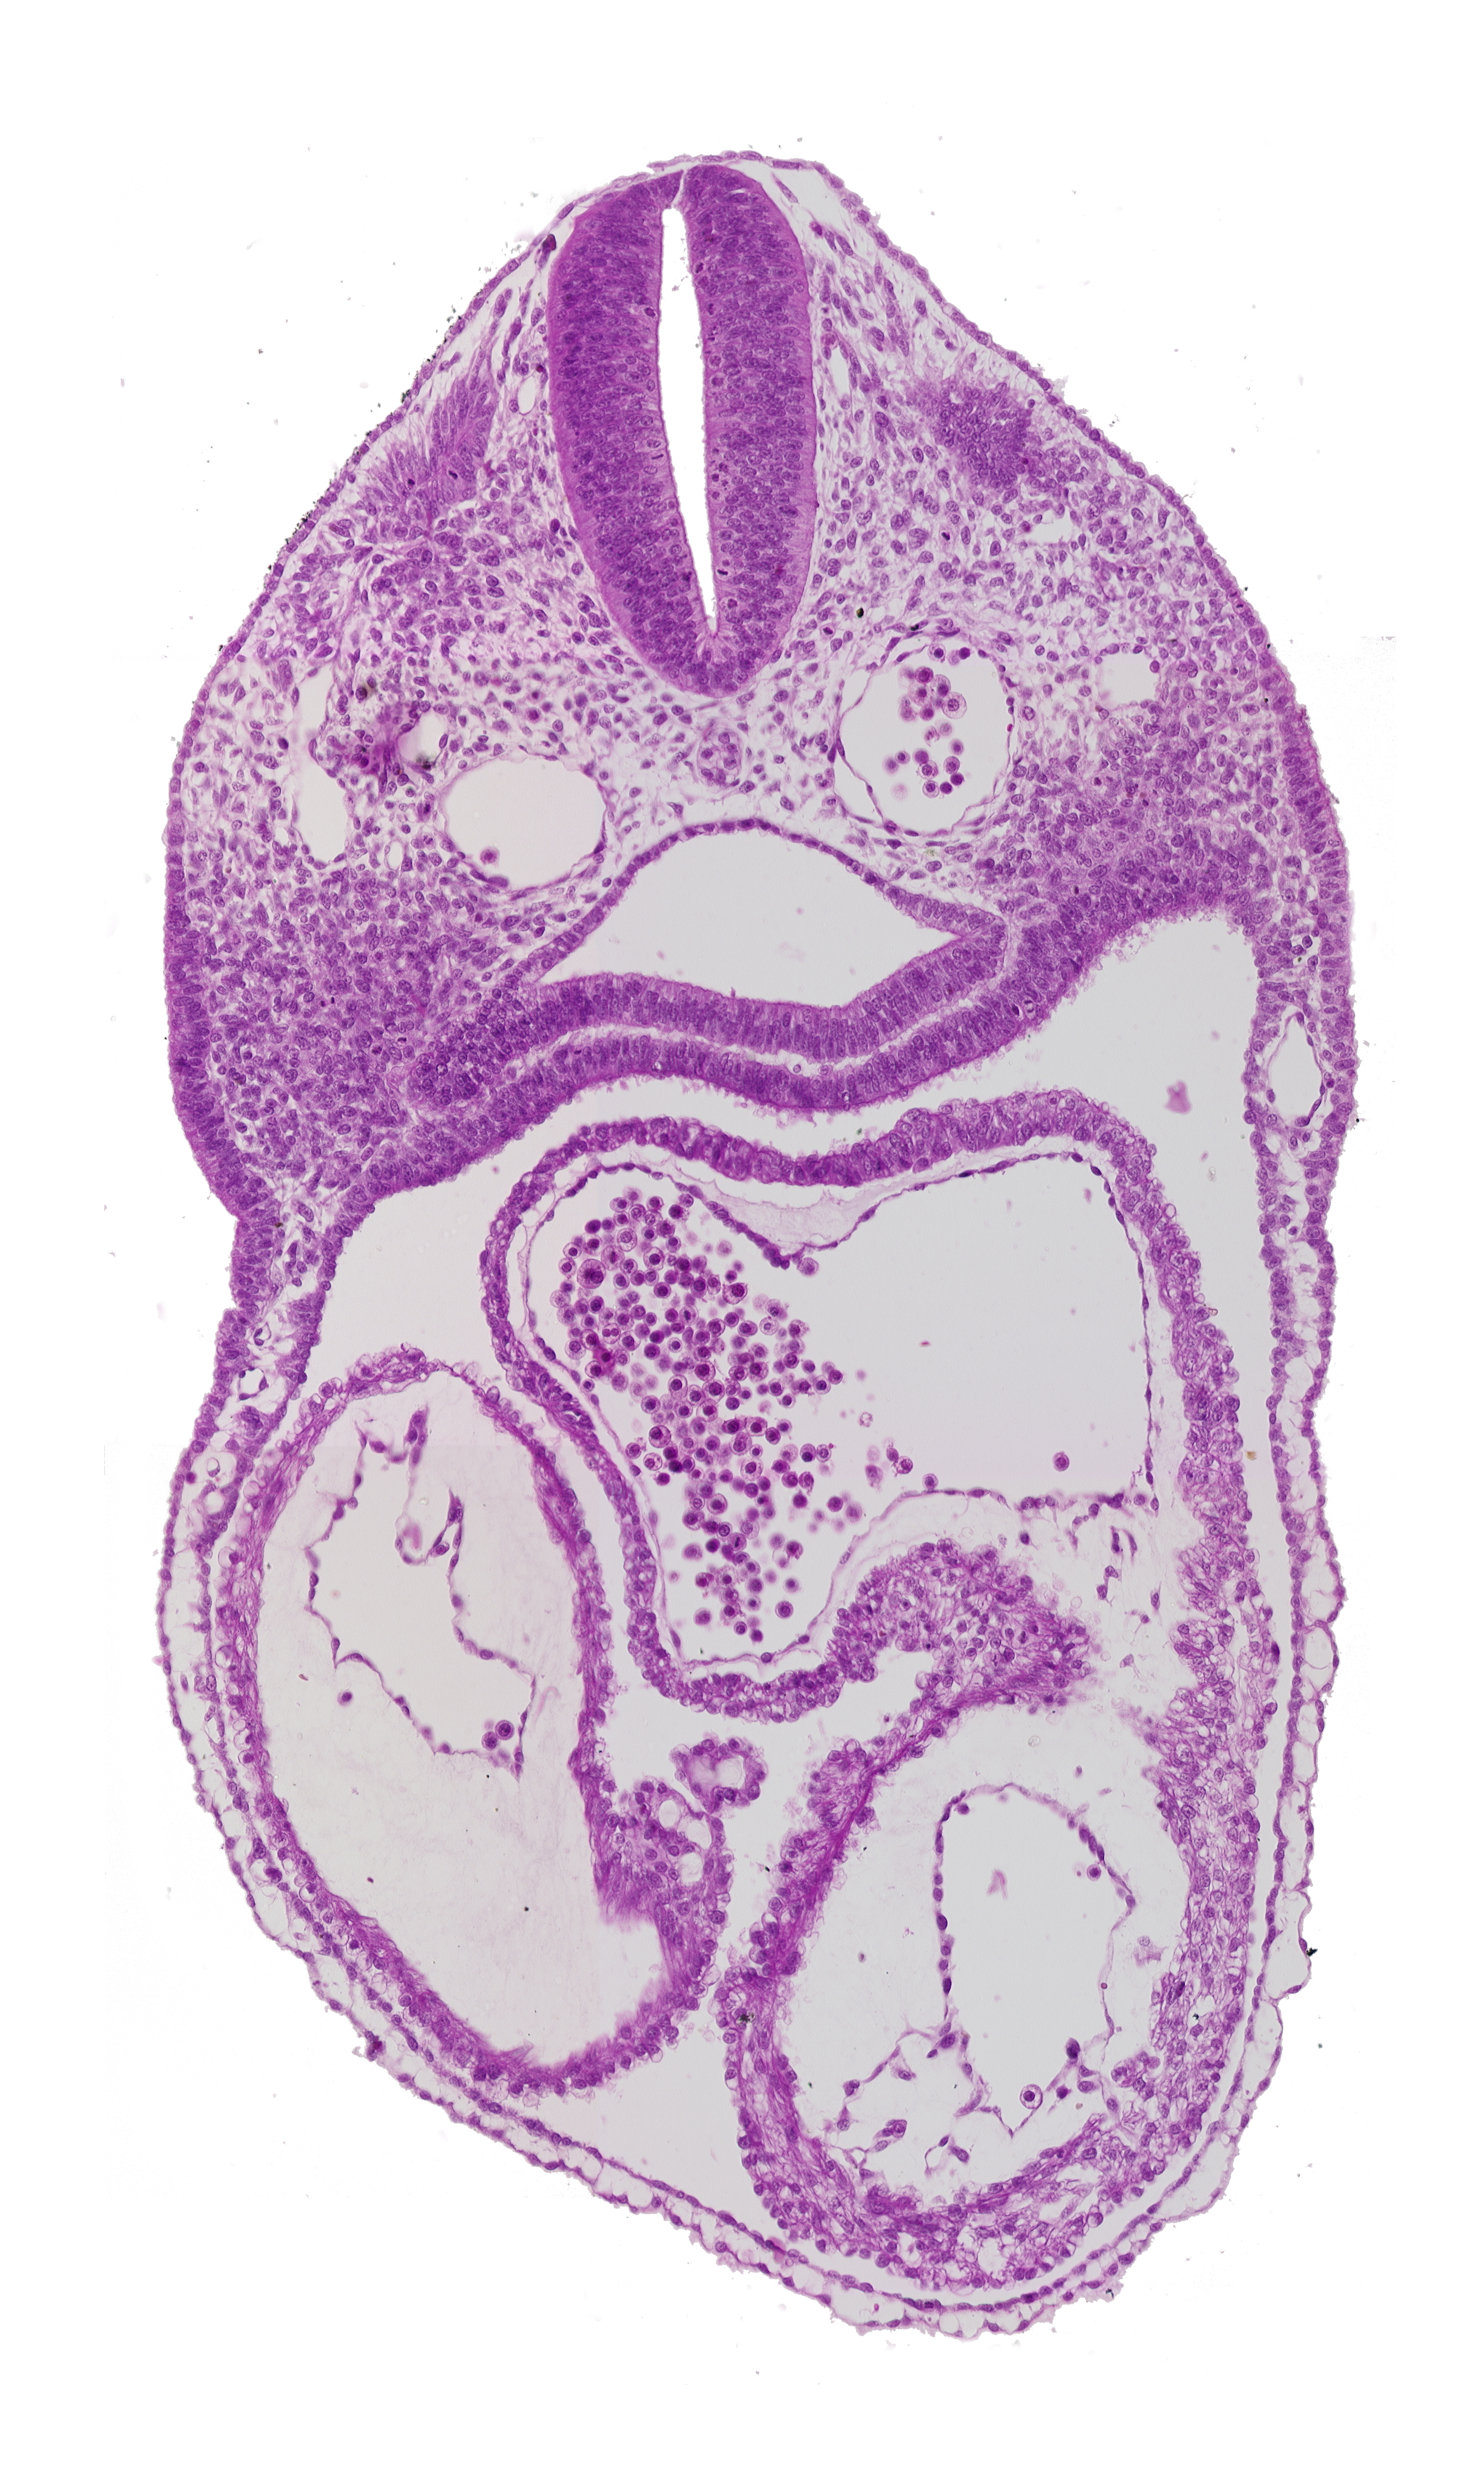

Carnegie Embryo #8943   |   Location: 04-02-01

Keywords: cardiac jelly, caudal part of dermatomyotome 3 (O-3), dorsal aorta, endocardium, epimyocardium, interatrial foramen (primum), left atrium, left ventricle, pharynx, precardinal vein, right atrium, right ventricle, ultimopharyngeal pouch